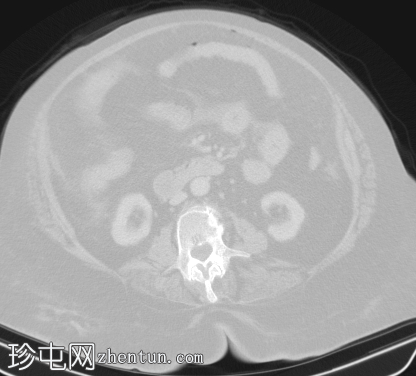

轴位

宫腔内可见气液平面,符合子宫蓄脓(宫腔内有脓液)。子宫前壁裂开,多个宫外气体灶延伸至腹膜外和腹膜内间隙,提示子宫穿孔。同时可见少量盆腔腹水和少量盆腔脂肪条索状改变。

其他发现:左侧附件囊肿、胆结石、双侧少量胸腔积液。